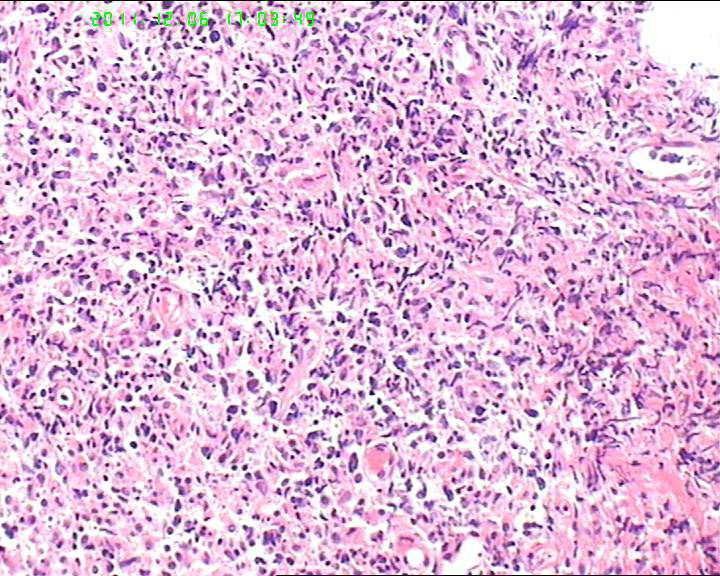

细胞异性明显,弥散分布,可见血管内皮异性明显,首先考虑血管肉瘤,恶黑,淋巴瘤?

组织内见大量形态各异的异型明显的细胞,弥漫分布,背景见肿瘤素质,首先考虑结外NK/T细胞淋巴瘤,鼻型;恶黑待排。